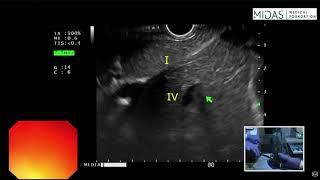

EUS evaluation of pancreas and surrounding structures (from Duo bulb)

Midas Gastro